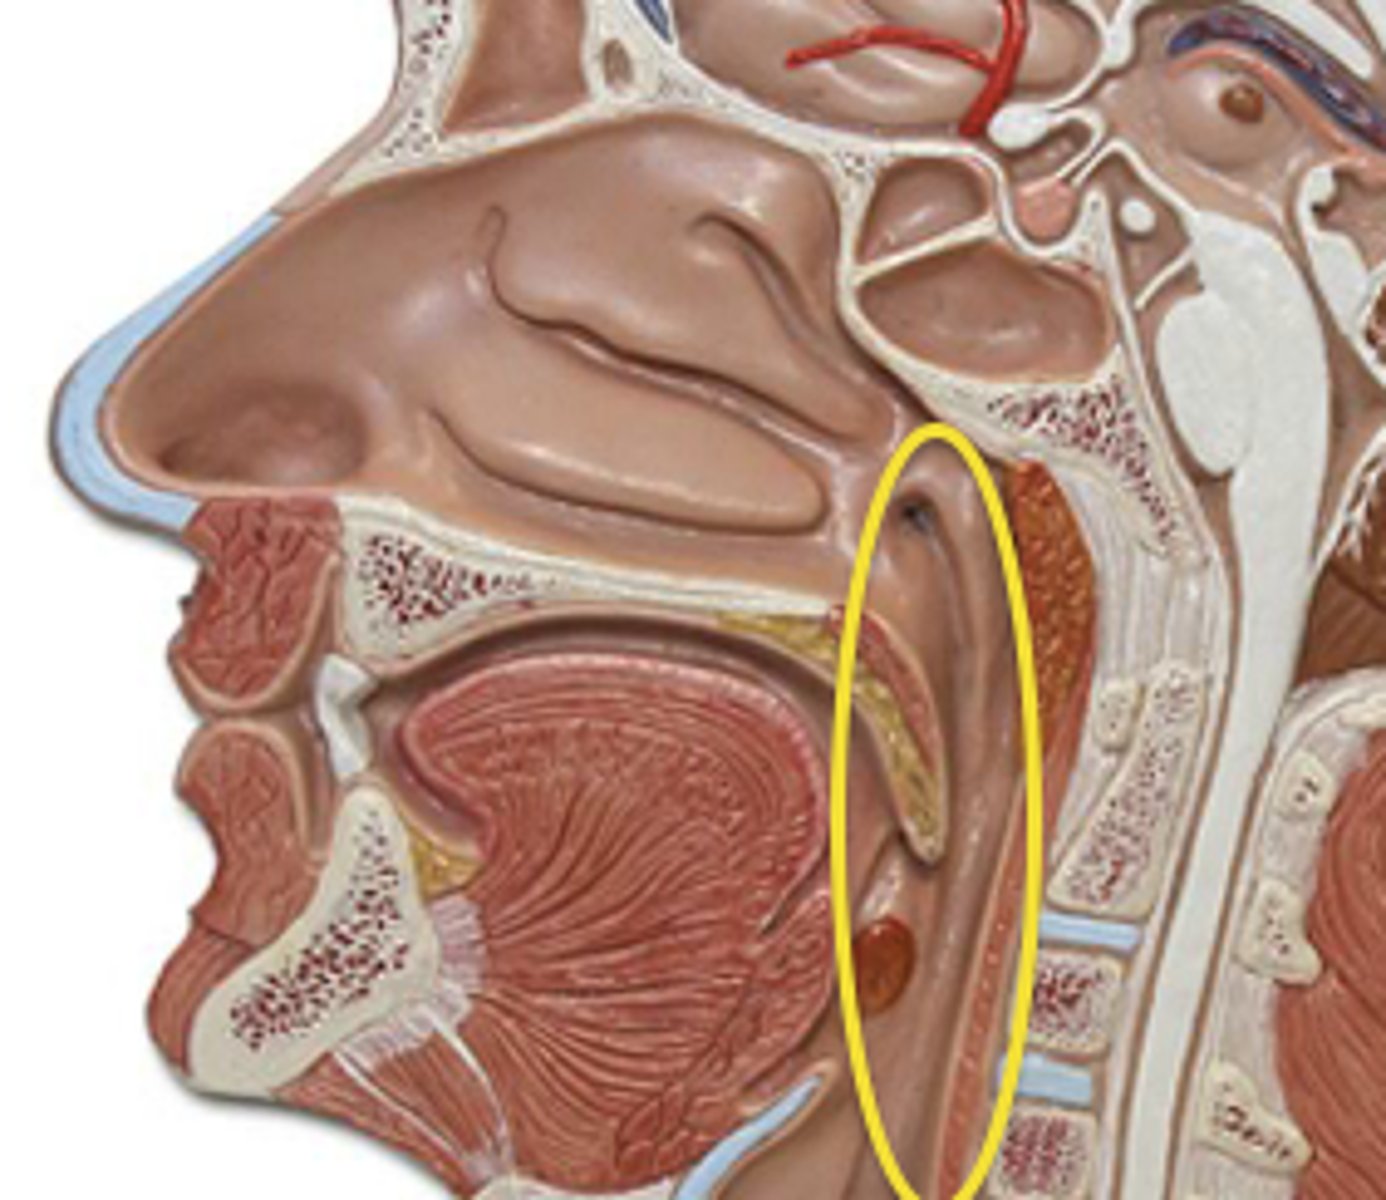

Thyropharyngeus Figure

Inferior Constrictor -

Thyropharyngeus Description

Inferior Constrictor consists of the

Thyropharyngeus and the Cricopharyngeus

Inferior Constrictor is thickest and strongest of constrictor muscles

Thyropharyngeus is the majority of the Inferior Constrictor

Origin -thyroid cartilage

Course - fans out posteriorly and medially

Insertion - midline raphe

Action - reduce diameter pharynx